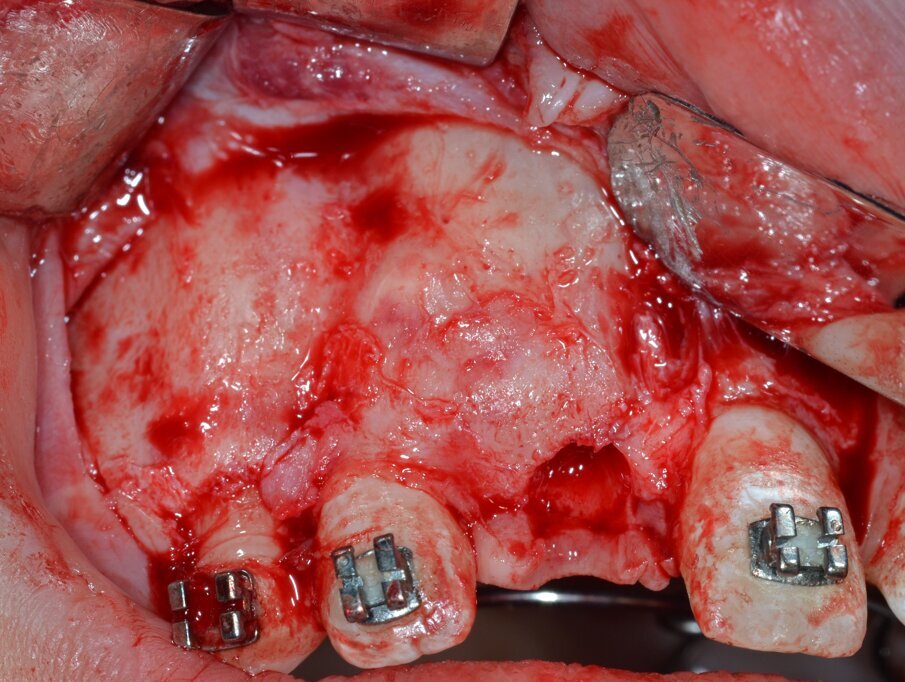

La neoformazione viene aggredita in due tempi operatori distinti: il primo tempo consiste nell’ostectomia per erosione della corticale ossea che la ricopre integralmente (Fig. 6) e, successivamente, viene effettuata un’osteotomia perilesionale alla ricerca del piano di clivaggio tra la neoformazione e il tessuto osseo circostante (Fig. 7).

Fig. 6_Ostectomia per erosione della corticale ossea.

Fig. 7_Osteotomia perilesionale che segue il contorno della neoformazione.

Fig. 8_Esposizione e isolamento della neoformazione.